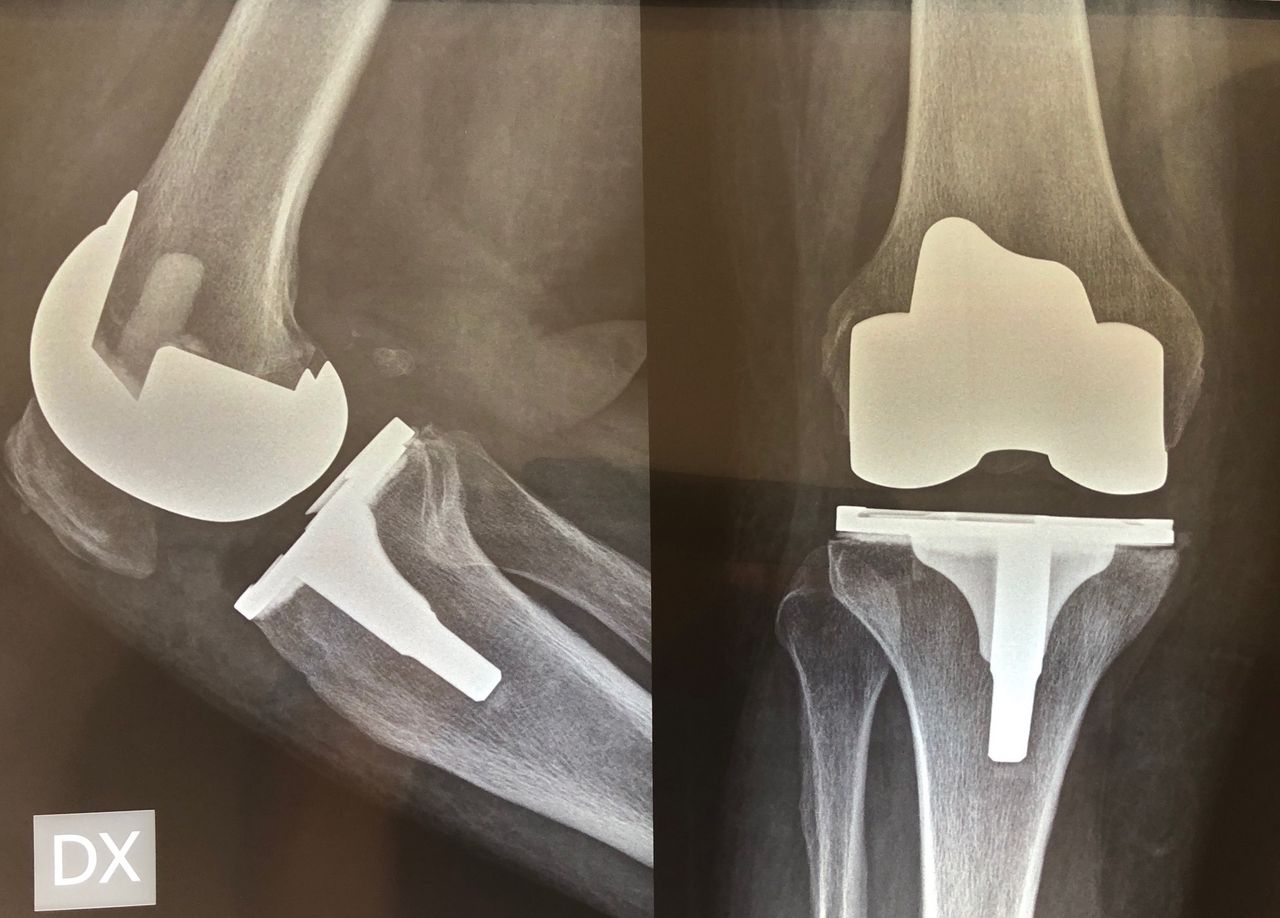

Sono specializzato nell'impianto di protesi di ginocchio ed anca in caso di patologie degenerative artritiche o necrotiche. Utilizzo protesi di ultima generazione, le protesi di ginocchio vengono applicate utilizzando una maschera creata su misura per ogni paziente, quelle di anca sono studiate per ridurre al minimo il rischio di lussazione (principale complicazione di questo tipo di intervento).

Foto e video